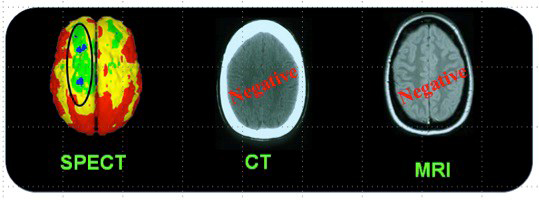

Figure 4 presents the case of a woman who sustained a mTBI in a rear-end car accident (without loss of consciousness). At the ED, CT imaging of head was normal and she was sent home. Unfortunately, she developed PPCS and sought neurologic opinion six months following the accident. An MRI of her brain was normal. Her PPCS symptoms persisted two more years. Brain SPECT imaging then revealed significant metabolic rCBF abnormalities underlying her PPCS. Studies have consistently demonstrated the superior sensitivity of functional imaging, such as SPECT and/or PET over CT and/or MRI to evaluate mTBI in the chronic setting. (10,11)

In conclusion, chronic mTBI is a very common and underdiagnosed source of morbidity and mortality in the US. Standard anatomical imaging with CT and MRI modalities are less sensitive to the neuropathological changes of mTBI in the chronic setting than functional brain imaging such as SPECT. Given its ability to penetrate the skull and address the neuronal mitochondrial dysfunction seen in mTBI, PBMT offers a non-toxic, non-invasive, safe and effective alternative to standard treatments. With its low cost and the convenience of in-home use, PBMT seems ideally positioned to address the silent epidemic of mTBI in the US.(14, 15)